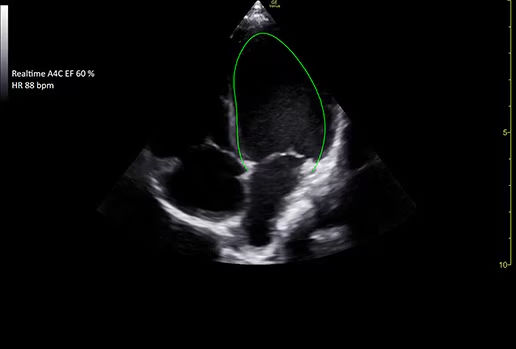

Access accurate, instant, and rapidly updating results with Real-Time EF

Capture precise results instantly without requiring ECGs through Real-Time EF*, an AI tool that continuously calculates real-time ejection fraction during live scanning in apical 4CH view.

featurecards-real-time-ef-desktop